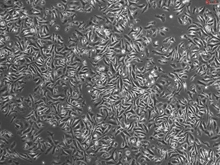

Macrophages are cells differentiated from circulating bone marrow-derived monocytes. The main function of macrophages is to remove cellular debris and destroy invading pathogens. Mouse Splenic Macrophages (MSMa) reside in the spleen and play a critical role in maintaining blood homeostasis [1]. There are three distinct populations of splenic macrophages including: red pulp macrophages, marginal zone macrophages, and marginal zone metallophillic macrophages [1, 2]. MSMa perform iron processing functions and aid in the capture of microbes and viruses in the circulatory system [1, 2]. Recent studies have shown that splenic macrophages contribute to stroke pathology and autoimmune diseases [3, 4]. MSMa are an excellent model for studying macrophage functions under normal physiological and pathological conditions.